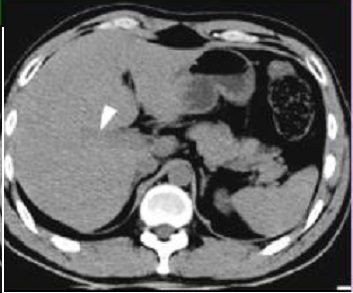

Image TDM de hepatite

: Aspect radiologique de

heaptite aigue du foie le plus souvent est image de

hepatomegalie : Depasse 15,5cm au line medio-clavuculaire

droit .Image de hypodense parenchymateuse . Image de oedeme

periportale ( aspect hypodensse peri portale ) .

Lymphadenopathie periportale et hepato-duoenale .

Aspect TDM de hepatite aigue

est image de hypoechogene dela parenchyme du foie ,

image de epaissisement de la paroi de la vesicule

biliaire . Coupe TDM axiale du foie |

Hepatite aigue : Aspect de

hypodense region perioportale et peri hillaire du

foie ( >5mm ) . Image de hypodense de la parenchyme

du foie . Lymphadenopathie hillare dans ce cas est

en bien se voyait . Image radiologique du foie

en coupe TDM axiale . |

Aspect hypodense du

parenchyme du foie dansd hepatite aigue . Le

foie est en moins densite que la rate . Et image de

hypodense region periportale et image de

adenopâthie hileire du foie . |

|